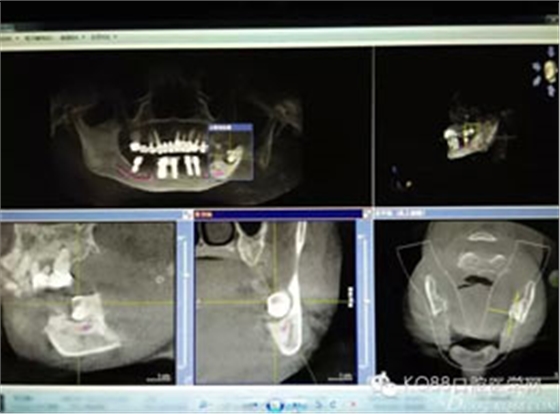

圖2.術(shù)前的CBCT影像檢查:38牙根尖靠近下頜神經(jīng)管。該CBCT是未帶烤瓷冠之前拍的。